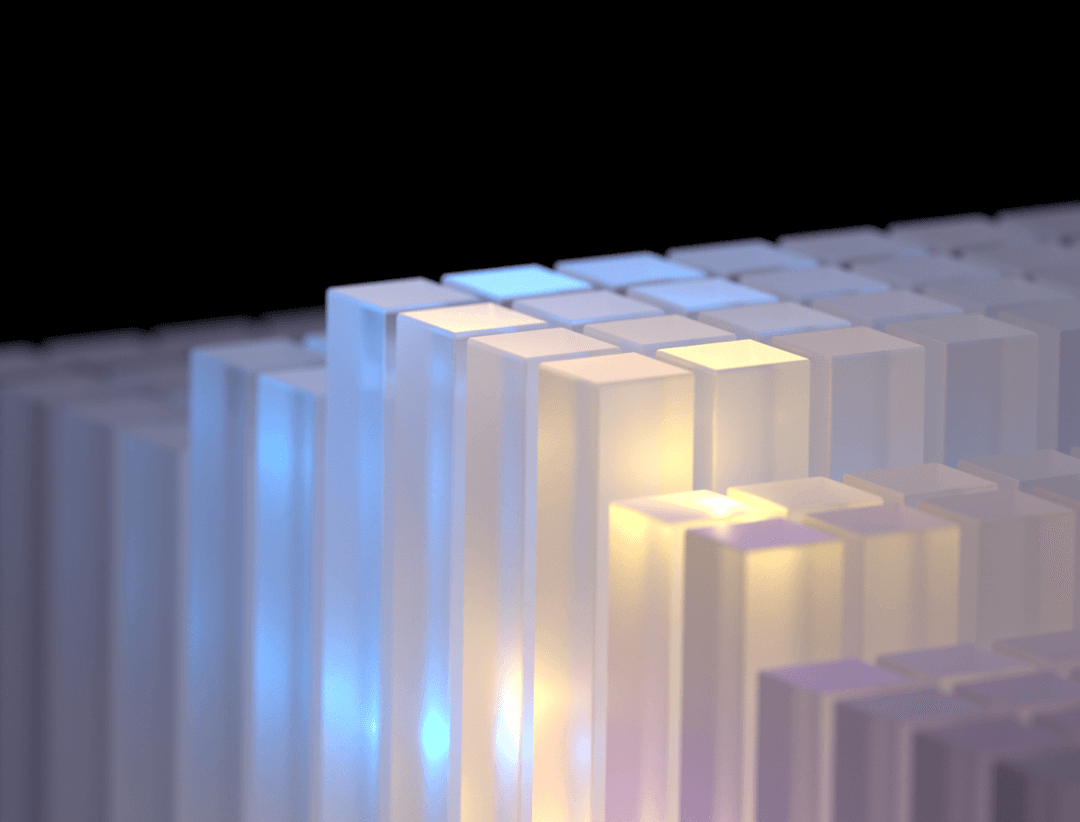

超清显像

超清NEMA分辨率成像

微小病灶无以遁形